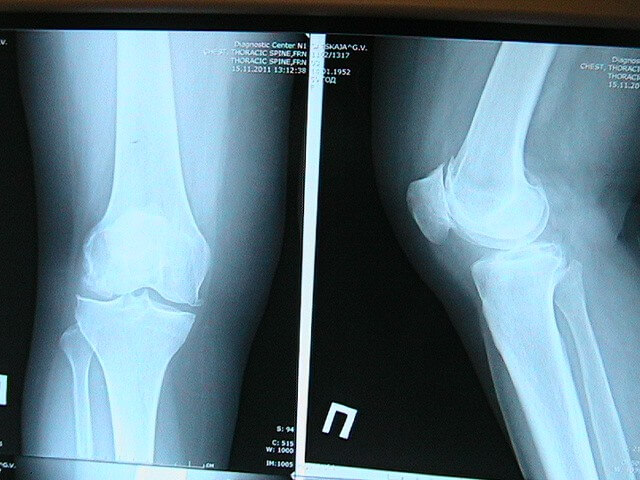

Рентген с контрастом

Учитывая, что обычный рентген не показывает состояние хрящей, мягких тканей, для получения достоверных снимков требуется введение в сустав определенных веществ.

Обычно пациенту в колено вводится непосредственно перед рентгеном контрастные жидкости и воздух. Конечно, цена в таких случаях будет включать кроме стоимости самого снимка и затраты на лекарство и услугу по обкалыванию коленного сустава.

Вводится средство в колено заранее. Перед этим сустав обкалывается анестетиками. Но не смотря на это пациент во время введения средства в колено может ощущать определенный дискомфорт или боль. После этого нужно пошевелить ногой, чтобы средство внутри сустава равномерно распределилось. В дальнейшем процедура проводится по отработанной, аналогичной обзорному рентгену, схеме.

Рентген позволяет врачу определить изменения в мягких тканях, произошедшие в коленном суставе. Но, чтобы оценить реальную картину довольно часто необходимо делать снимки в двух, а то и в нескольких проекциях. Рентген с контрастом позволяет определить состояние менисков, сухожилий и связок.

Однако после введения контрастирующей жидкости возможны осложнения в виде хруста или аллергических реакций. Избежать таких последствий можно при соблюдении техники проведения манипуляций.